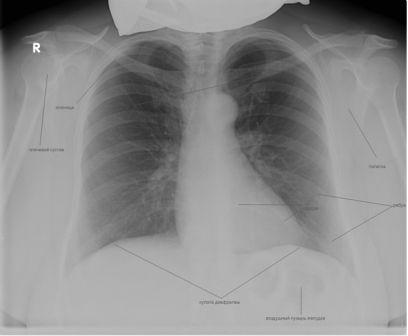

Рентгенологический снимок органов грудной клетки в прямой проекции представляет собой суммарное плоскостное изображение легких, сердца, органов средостения и ребер.

Анатомические структуры на снимке

Какие органы отображает снимок:

- крупные симметричные просветления с обеих сторон обусловлены воздушными легкими;

- в центральной части – тень сердца;

- купола диафрагмы – прослеживаются в нижней части снимка;

- передние и задние отрезки ребер формируют решетчатую структуру снимка;

- в проекции мягких тканей в периферической части рентгенограммы прослеживаются плечевые суставы.

Обратим внимание читателей, что плотность вышеописанных структур отличается, что обусловлено различным содержанием в них кальция, жидкости и воздуха. Известно, что от плотных структур рентгеновские лучи сильно отражаются, а через воздушные легко проходят, не создавая четкой структуры на снимке. Чтобы рентгенологи смогли более точно описывать картинку, созданы понятия «тень» и «просветление».

Просветление указывает на участок повышенной воздушности, а тень – на более плотный очаг. На вышеописанном снимке легкие представляют собой просветление, а сердце – тень (затемнение).